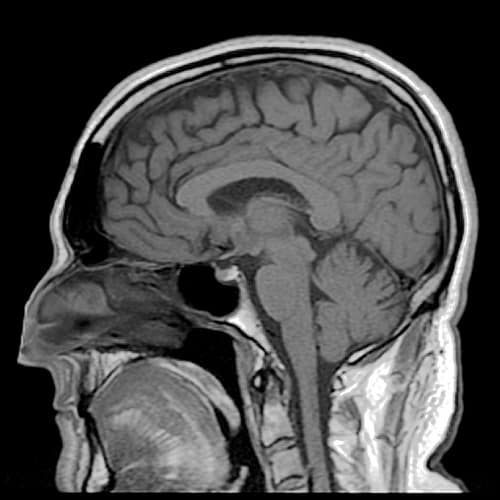

L’obstruction d’une artère par un caillot sanguin (thrombose) est la première cause de mortalité dans le monde. Elle entraîne des Accidents Vasculaires cérébraux (AVC) et ischémiques, des infarctus du myocarde et ischémies de membre. Pour rappel, lorsque la thrombose survient, il s’agit d’une urgence thérapeutique : il faut détruire le caillot au plus vite afin de rétablir le flux sanguin et éviter des dommages irréversibles.